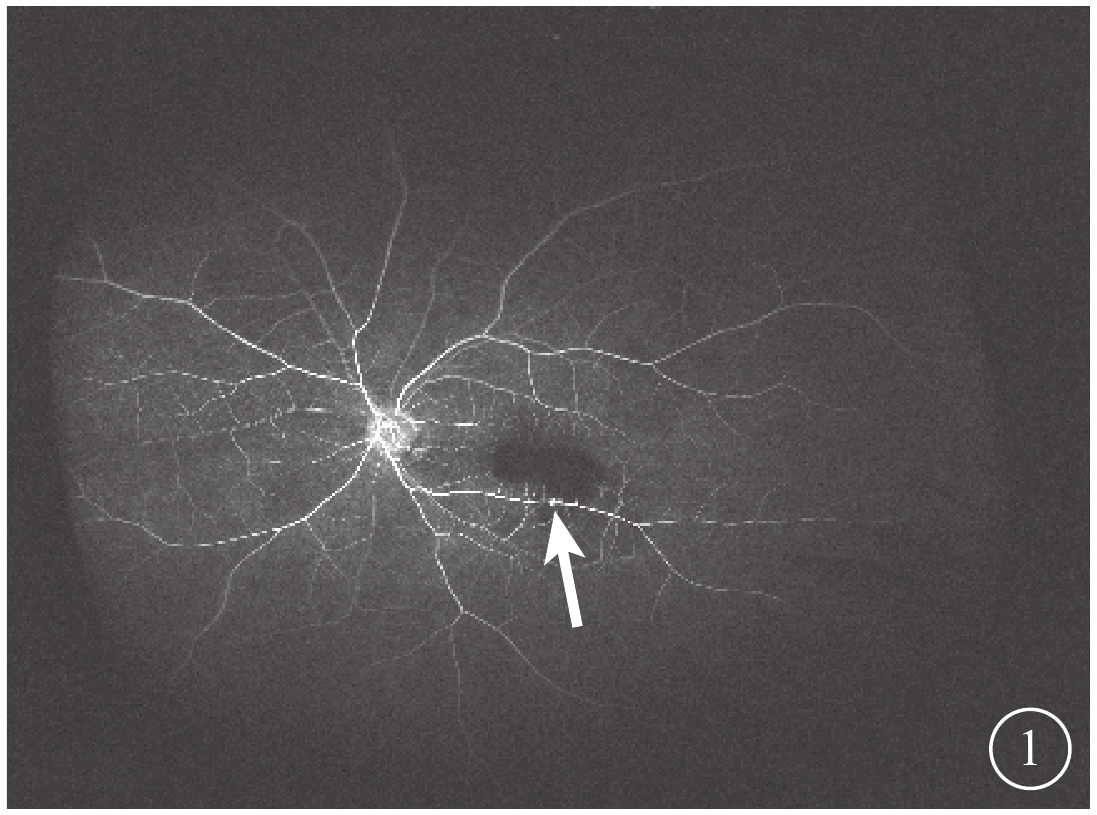

3只眼均行常規全身檢查及最佳矯正視力(BCVA)、眼壓、裂隙燈顯微鏡、眼底彩色照相、眼部B型超聲、熒光素眼底血管造影(FFA)及光相干斷層掃描(OCT)等眼部檢查。患眼BCVA為手動/20 cm~0.06,平均BCVA為0.03±0.02。眼壓為7.9~18.9 mmHg(1 mmHg=0.133 kPa),平均眼壓為(9.87±3.23)mmHg。3只眼均存在不同程度的晶狀體混濁。RAM位于視網膜顳上2只眼,位于視網膜顳下1只眼。黃斑區內界膜下出血大小為1.5~8.0倍視盤面積。FFA檢查發現,動脈期患眼顳下視網膜動脈分支處強熒光點,周圍出血遮蔽視網膜及脈絡膜熒光(圖1)。OCT檢查發現,患眼出血灶表面可見一弧形強反射條帶,且與內界膜相對應,其下呈點狀強反射(圖2)。

圖1

患眼FFA像。動脈期視網膜顳下可見強熒光點(白箭),上方出血遮蔽熒光

圖1

患眼FFA像。動脈期視網膜顳下可見強熒光點(白箭),上方出血遮蔽熒光

3只患眼經FFA檢查均可見動脈期顳側視網膜動脈分支處強熒光點,周圍出血遮蔽視網膜及脈絡膜熒光;OCT檢查可見出血灶表面一弧形強反射條帶,且與內界膜相對應,其下呈點狀強反射。證明其RAM及內界膜下出血診斷成立[5]。

3只眼均行常規全身檢查及最佳矯正視力(BCVA)、眼壓、裂隙燈顯微鏡、眼底彩色照相、眼部B型超聲、熒光素眼底血管造影(FFA)及光相干斷層掃描(OCT)等眼部檢查。患眼BCVA為手動/20 cm~0.06,平均BCVA為0.03±0.02。眼壓為7.9~18.9 mmHg(1 mmHg=0.133 kPa),平均眼壓為(9.87±3.23)mmHg。3只眼均存在不同程度的晶狀體混濁。RAM位于視網膜顳上2只眼,位于視網膜顳下1只眼。黃斑區內界膜下出血大小為1.5~8.0倍視盤面積。FFA檢查發現,動脈期患眼顳下視網膜動脈分支處強熒光點,周圍出血遮蔽視網膜及脈絡膜熒光(圖1)。OCT檢查發現,患眼出血灶表面可見一弧形強反射條帶,且與內界膜相對應,其下呈點狀強反射(圖2)。

圖1

患眼FFA像。動脈期視網膜顳下可見強熒光點(白箭),上方出血遮蔽熒光

圖1

患眼FFA像。動脈期視網膜顳下可見強熒光點(白箭),上方出血遮蔽熒光

3只患眼經FFA檢查均可見動脈期顳側視網膜動脈分支處強熒光點,周圍出血遮蔽視網膜及脈絡膜熒光;OCT檢查可見出血灶表面一弧形強反射條帶,且與內界膜相對應,其下呈點狀強反射。證明其RAM及內界膜下出血診斷成立[5]。